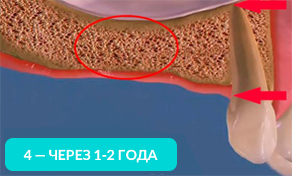

Уже через год костная ткань значительно истончается! В таких условиях нельзя установить имплант зуба без наращивания костной ткани.